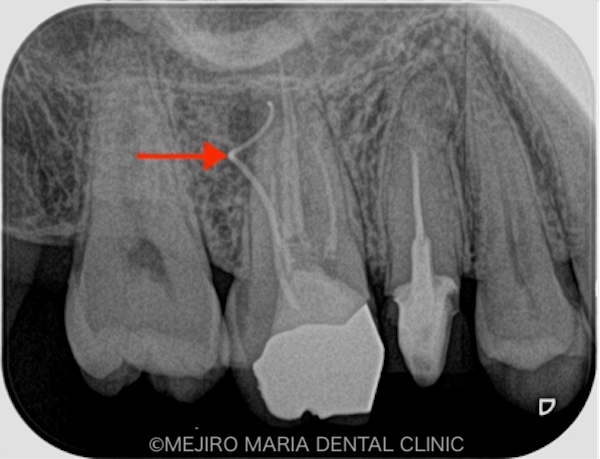

右上の歯を確認したとろ、当該部位にはフィステル(瘻孔)が確認でき、フィステルより造影してみると、右上6番の歯の根尖部付近から、排膿されていることがわかりました(写真の赤矢印)。フィステル以外に痛みなどの所見は見当たらないものの、「根尖性歯周炎」と診断し、治療を開始しました。

右上6番の歯に確認できたフィステル(瘻孔)は、2回目の根管治療の際にはすでに消失していました。患者様のご希望により、すでに根管治療がされている手前側の歯(右上5番)も、根管治療をやり直すこととなりました。